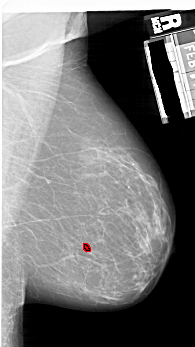

A_1925_1.RIGHT_CC

RIGHT_CC LINES 5431 PIXELS_PER_LINE 3451 BITS_PER_PIXEL 12 RESOLUTION 43.5 OVERLAY

FILE: A_1925_1.RIGHT_CC.OVERLAY

TOTAL_ABNORMALITIES 1

ABNORMALITY 1

LESION_TYPE CALCIFICATION TYPE PLEOMORPHIC DISTRIBUTION CLUSTERED

ASSESSMENT 4

SUBTLETY 3

PATHOLOGY BENIGN

TOTAL_OUTLINES 1

BOUNDARY